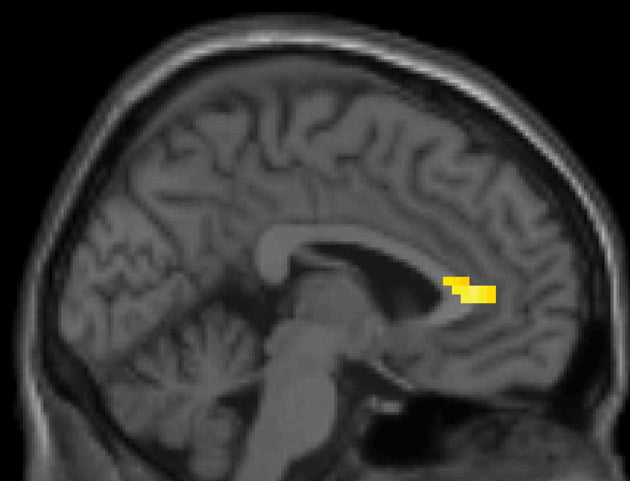

Bijna alle beheerders deden de belofte om het geld te delen, maar die kwamen ze lang niet allemaal na. En dat konden de onderzoekers zien met behulp van fMRI-scans. Bij een belofte die niet nagekomen werd, was er namelijk een verhoogde hersenactiviteit te zien in bepaalde hersendelen (te weten: de dorsolaterale prefrontale cortex, de cortex cingularis anterior en de amygdala).

Opmerkelijk is hierbij dat de verhoogde hersenactiviteit plaatsvond op het moment dat die belofte werd gedáán. Volgens Baumgartner is dat verrassend, want in principe heeft iemand die iets belooft dan nog niets fout gedaan. Sterker nog, op dat moment kan hij de belofte nog steeds nakomen. De hersenen weten dus blijkbaar van tevoren al of iemand de kluit gaat belazeren.